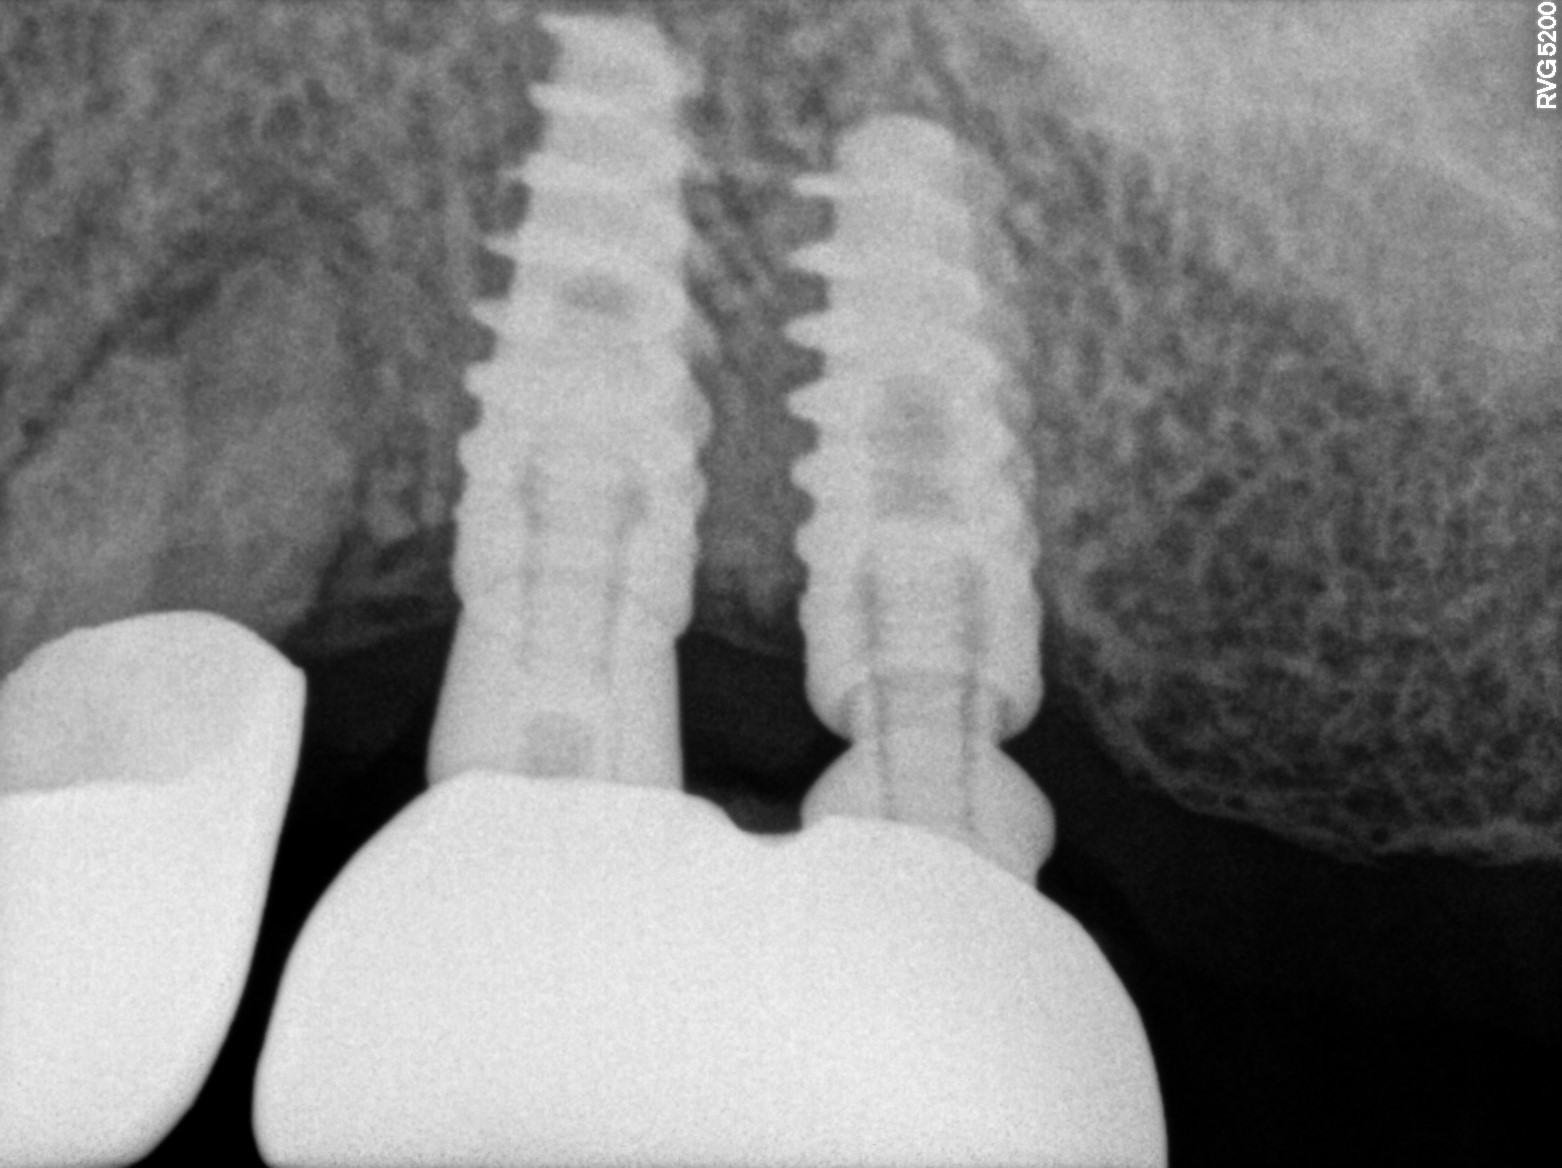

Dental Radiographs FHIR: DocumentReference · LOINC 24641-7

R55.jpg

24641-7

| Dental implant placement | 234781005 | D6010 Surgical placement of implant body | ##44, #45, #47 | 2023-03-13 | completed | abutment placed 44 & 45 & 47 | |

| Dental implant placement | 234781005 | D6010 Surgical placement of implant body | — | 2023-02-13 | completed | 5 healing abutment placed | |

| Dental implant placement | 234781005 | D6010 Surgical placement of implant body | ##44, #45, #47, #75, #11, #14, #15 | 2022-11-25 | completed | implant placed & 44 & 45 & 47-3-75*11-5 & t-30 & 14--4-2*10 & 15--3-75*10 & t-10 | |

| Dental implant placement | 234781005 | D6010 Surgical placement of implant body | — | 2022-08-04 | completed | abutment placed | |